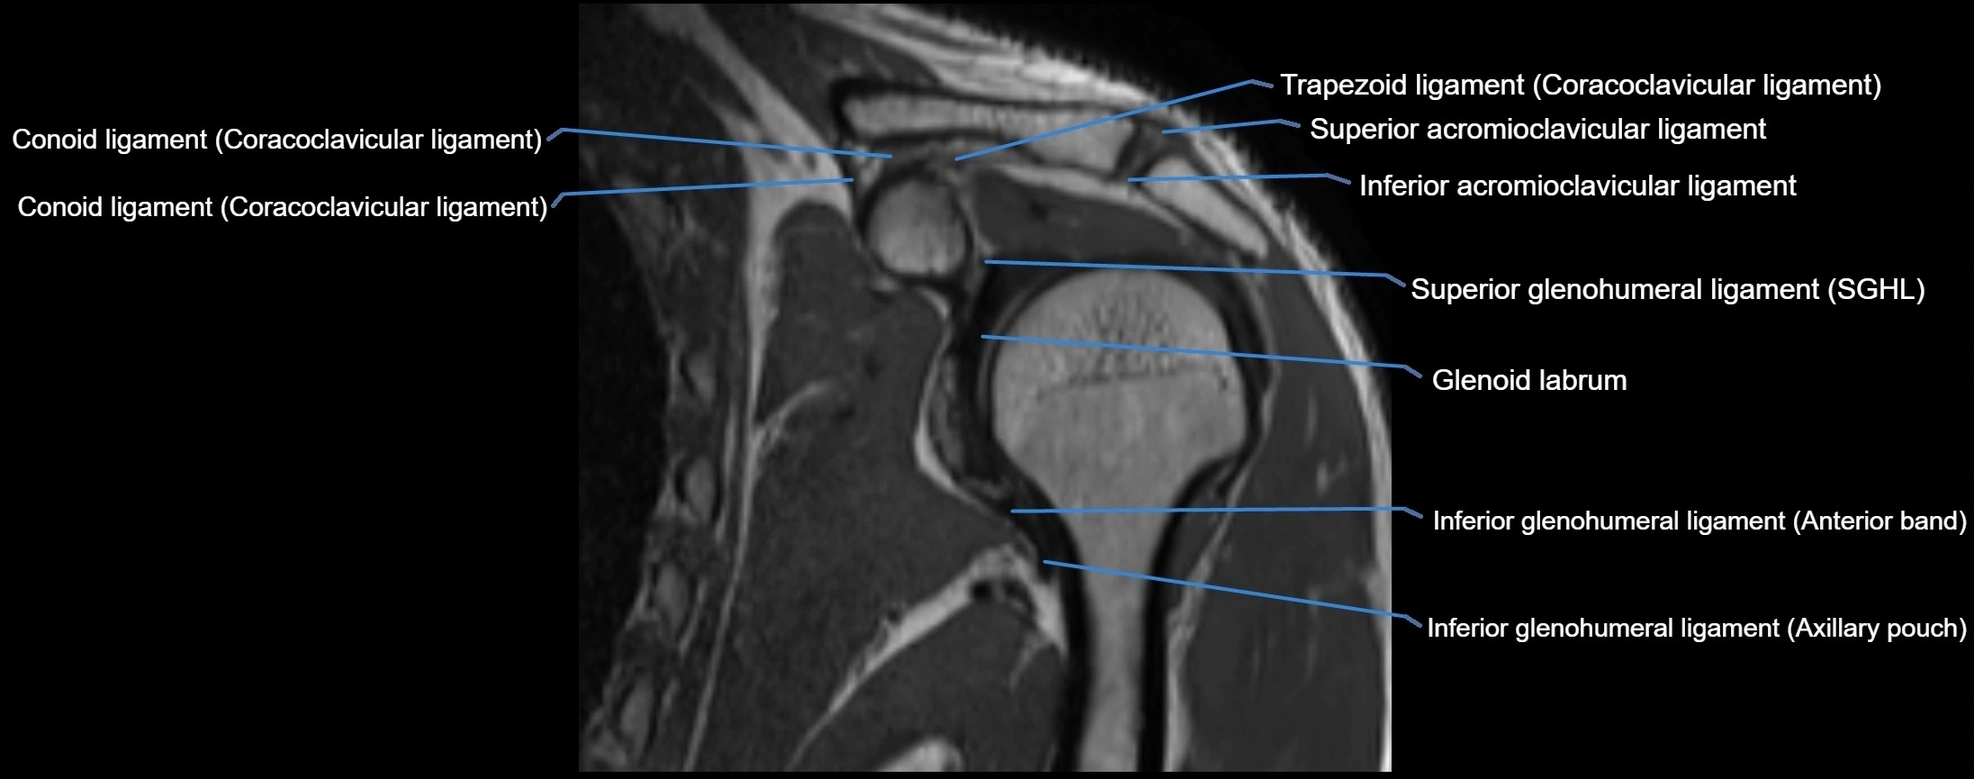

MRI images

image